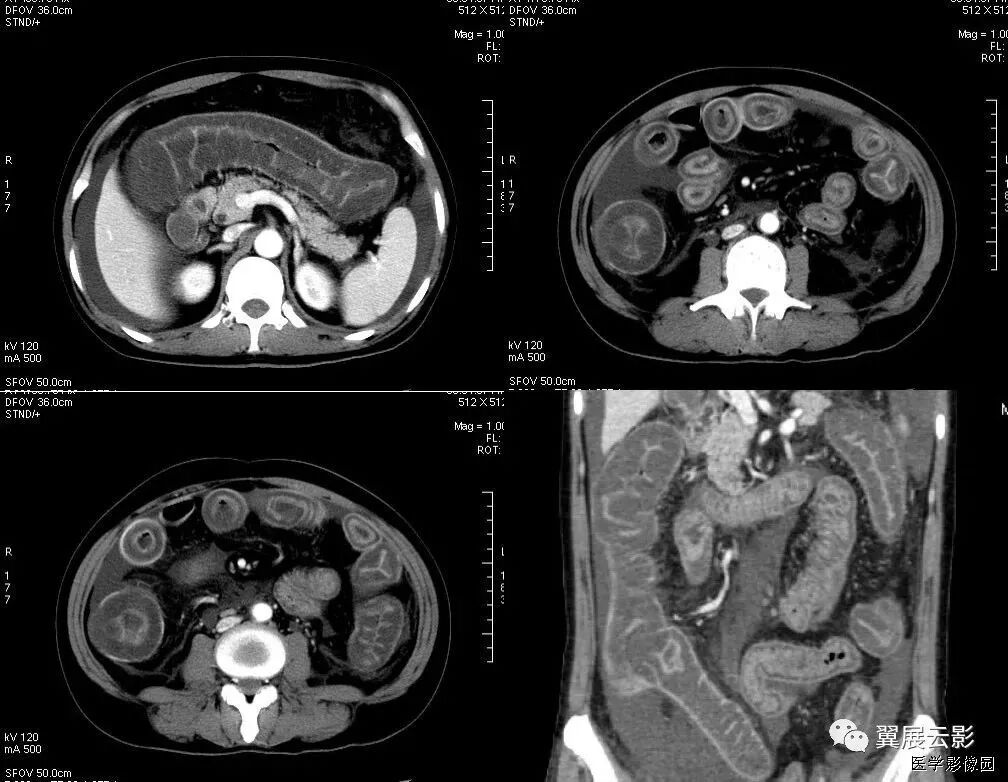

7、腹茧症

全部或部分小肠被一层致密、灰白色的纤维膜所包裹,形似“蚕茧”,故称为腹茧症,又称为特发性硬化性腹膜炎、小肠禁锢症、小肠纤维膜包裹症等。多见于青春期女性。腹部CT十二指肠空肠交界处扭曲,肠系膜增厚伴上消化道扩张,提示不全性肠梗阻。X线可发现全部或部分小肠聚拢于某一部分,位置固定。CT检查有更助于腹茧症的术前诊断。CT能显示梗阻程度及包块内肠管的情况,还能显示包裹在肠管周围的纤维包膜。一旦观察到包膜便可诊断腹茧症。典型的CT表现为扩张的小肠肠袢固定在腹部的某一部位,并被增厚的包膜所包裹或分割。增强扫描示包膜强化明显,部分病例可见腹腔积液及肠管间积液。

鉴别诊断:需要与腹膜包裹症鉴别

不全肠梗阻